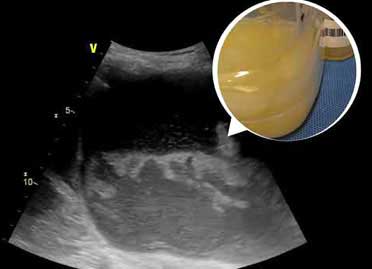

Empyema is a collection of pus in between the lung and chest wall formed by two pleural layers, visceral and pariteal. Read More >>